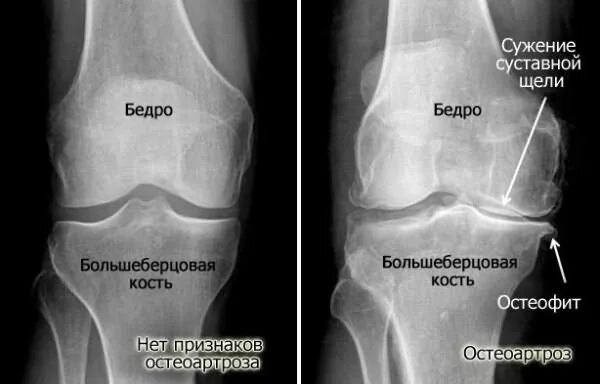

Суставная щель коленного сустава норма